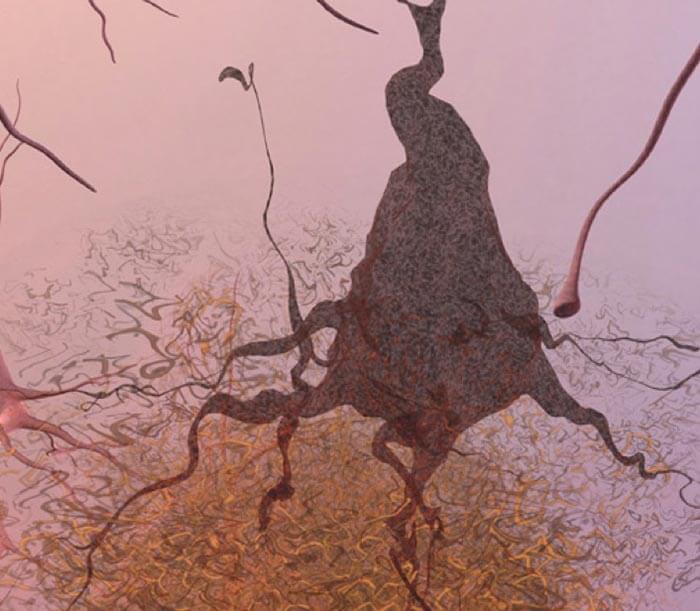

Under the Microscope

Scientists can also see the terrible effects of Alzheimer's disease when they look at brain tissue under the microscope. Scientists are not absolutely sure what causes cell death and tissue loss in the Alzheimer's brain, but the plaques and tangles in the figures below are prime suspects.

Alzheimer's tissue has many fewer nerve cells and synapses than a healthy brain.

Plaques, abnormal clusters of protein fragments, build up between nerve cells.

Dead and dying nerve cells contain tangles, which are made up of twisted strands of another protein.

More About Tangles

Tangles destroy a vital cell transport system made of proteins. This electron microscope picture shows a cell with some healthy areas and other areas where tangles are forming.

In healthy areas:

In areas where tangles are forming:

Nutrients and other essential supplies can no longer move through the cells, which eventually die.